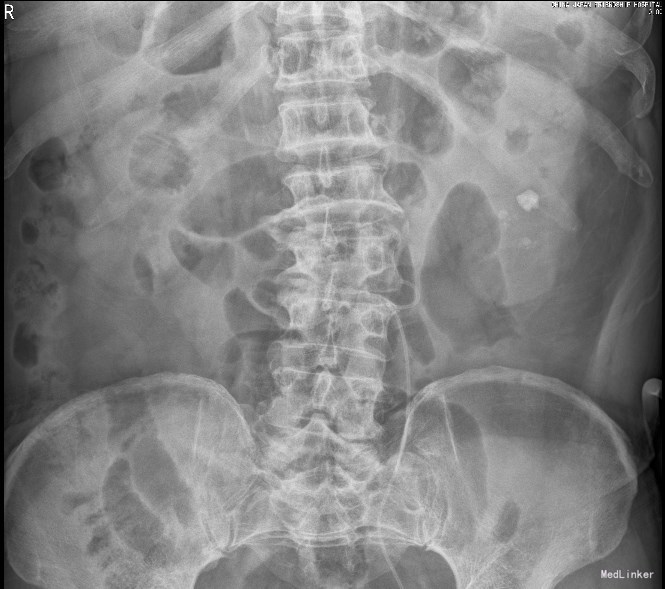

患者男,63岁,主因“查体发现左肾及输尿管结石1个月”以“左侧肾输尿管结石”收入院。 一、病例特点: (1)老年男性患者,隐匿起病。 (2)患者1个月前无明显诱因出现双下肢肿胀,偶有左下腹绞痛,疼痛可忍受,尿中带泡沫,于当地医院就诊,诊断“左侧肾输尿管结石,左侧无功能肾”,建议行左肾切除

2015年10月20日,泌尿系CT,左侧输尿管上段结石并左侧肾盂积水,左肾盂结石